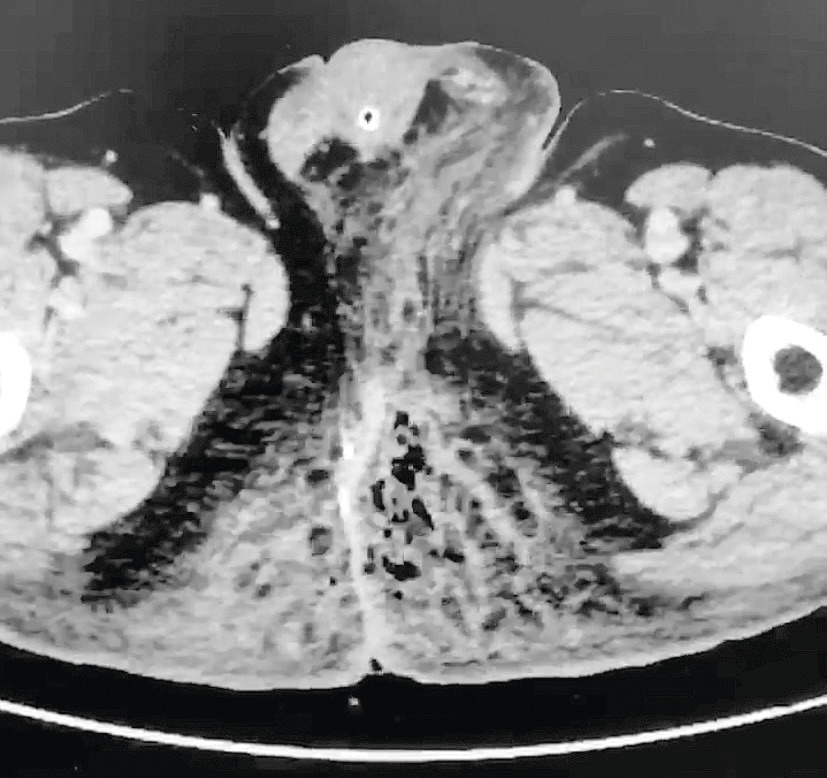

Un homme de 45 ans, diabétique, consulte aux urgences pour une douleur anale, pour laquelle il prend des anti-inflammatoires non stéroïdiens (AINS) depuis quatre jours. À l’examen, un érythème des deux fesses s’étend vers le scrotum (fig. 1).

Il s’agit d’une urgence, car elle peut rapidement évoluer vers une défaillance multiviscérale. Il est important de ne pas méconnaître ce diagnostic ; en effet, les signes locaux du début ont une allure banale mais peuvent rapidement évoluer. Ainsi, le placard cutané, initialement érythémateux et œdémateux, devient ensuite infiltré et d’extension rapide vers le scrotum, les plis inguinaux, les lombes, etc. Le crépitement sous-cutané et le suintement verdâtre fétide caractéristiques sont tardifs. À ce stade, les signes systémiques (fièvre ou hypo­thermie, collapsus, confusion, etc.) sont quasiment constants. La mise en évidence de « bulles » en tomodensitométrie (fig. 2) est également caractéristique.